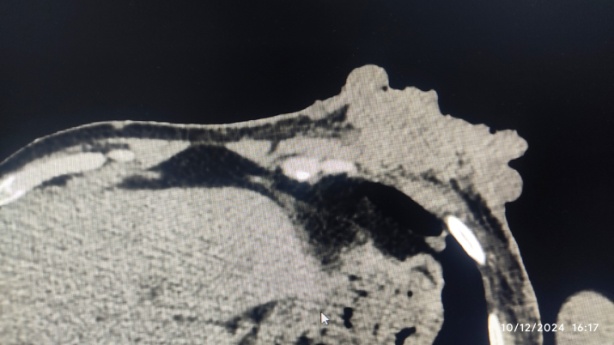

In the setting of multiple neurofibromas, the possibility of sarcoma in the setting of neurofibromas was suspected, and the patient was subjected to fine needle aspiration cytology, which showed malignant duct epithelial cells in clusters suggesting duct carcinoma of the breast. Then, the patient was subjected to a CT scan (fig. 3), which showed a soft tissue tumor in the subcutaneous plane with surface ulceration and axillary lymphadenopathy.

Fig. 3: CT scan showing ulcerating soft tissue lesion in left anterior chest wall infiltrating pectoralis major muscle